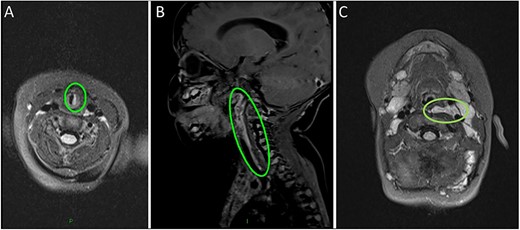

Magnetic resonance imaging (MRI) head/neck took place due to the presence of a facial plaque haemangioma (increased risk of PHACE syndrome) revealing an incidental lobulated lesion within the deep soft tissues of the left neck, measuring 2.7 × 7.4 cm with hyper-intense signal from the left carotid sheath (Fig. 2). The lesion extended from the skull base superiorly to the mediastinum inferiorly involving the left carotid space. The lesion extended between the internal and external carotid arteries. There was associated mass effect with effacement of the left pharyngeal mucosal space and left posterior oropharynx.

(A) MRI scan highlighting the subglottic infantile haemangioma. (B–C) Sagittal and axial MRI images of the carotid sheath haemangioma.